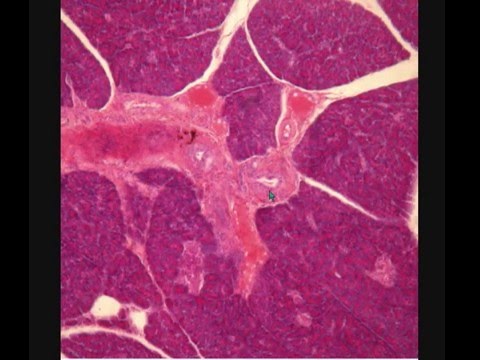

ПОДЖЕЛУДОЧНАЯ ЖЕЛЕЗА PANCREAS гистологическое строение

Сазонов С.В. - зав. кафедрой гистологии УГМУ

Электронный образовательный ресурс поможет Вам изучить основные структурные элементы (в соответствии с современной Международной морфологической номенклатурой терминов) гистологического среза поджелудочной железы в световом микроскопе